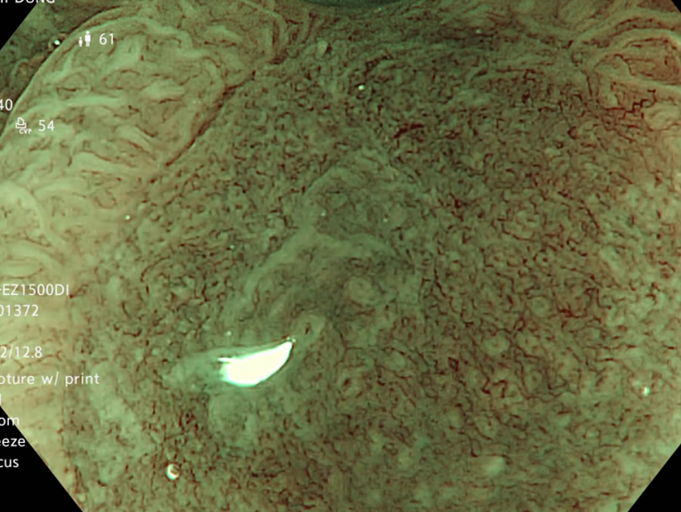

Kết quả nội soi đại tràng: có 3 polyp đại tràng (Paris Is, Kudo IIIL) (đã được cắt polyp qua nội soi), đại tràng sigmoid đã cắt một phần, tổn thương lồi đại trực tràng dạng polyp không cuống, ranh giới rõ, bề mặt màu hồng, có nhiều polyp có lớp nhầy ở trên bề mặt và thấy có hình ảnh da gà xung quanh tổn thương. Trên hình ảnh M-NBI thấy các tổn thương có các tuyến giãn nhẹ nhưng còn đều, mạch máu giãn nhẹ, chưa có biến đổi hình dạng --> đã tiến hành sinh thiết

Hình 2: Hình ảnh nội soi đại tràng

Tổn thương trên nội soi là hình ảnh các tổn thương lồi tại đại trực tràng dạng polyp không cuống, ranh giới rõ, bề mặt màu hồng, có nhiều polyp có lớp nhầy ở trên bề mặt. Chúng tôi nghĩ đến đây là hình ảnh của đa polyp mũ đại tràng mặc dù kết quả mô bệnh học chỉ kết luận là tổn thương viêm trợt mạn tính đang hoạt động, tạo hình ảnh giả polyp. Do trước đó cô ấy đã trải qua nhiều phương pháp điều trị theo hướng viêm ruột như kháng sinh Tinidazol, Levofloxacin, mesalazine… nhưng tình trạng đại tiện nhiều lần không được cải thiện, cùng với đó chúng tôi ghi nhận thấy có sự hiện diện của vi khuẩn H.pylori ở dạ dày. Vì vậy chúng tôi đã quyết định điều trị diệt trừ vi khuẩn H.pylori bằng phác đồ 4 thuốc: Tetracyclin 2g/ngày, Tinidazol 1,5g/ngày, Esomeprazol 80 mg/ngày, Bismuth 480 mg/ngày, thời gian điều trị là 2 tuần.